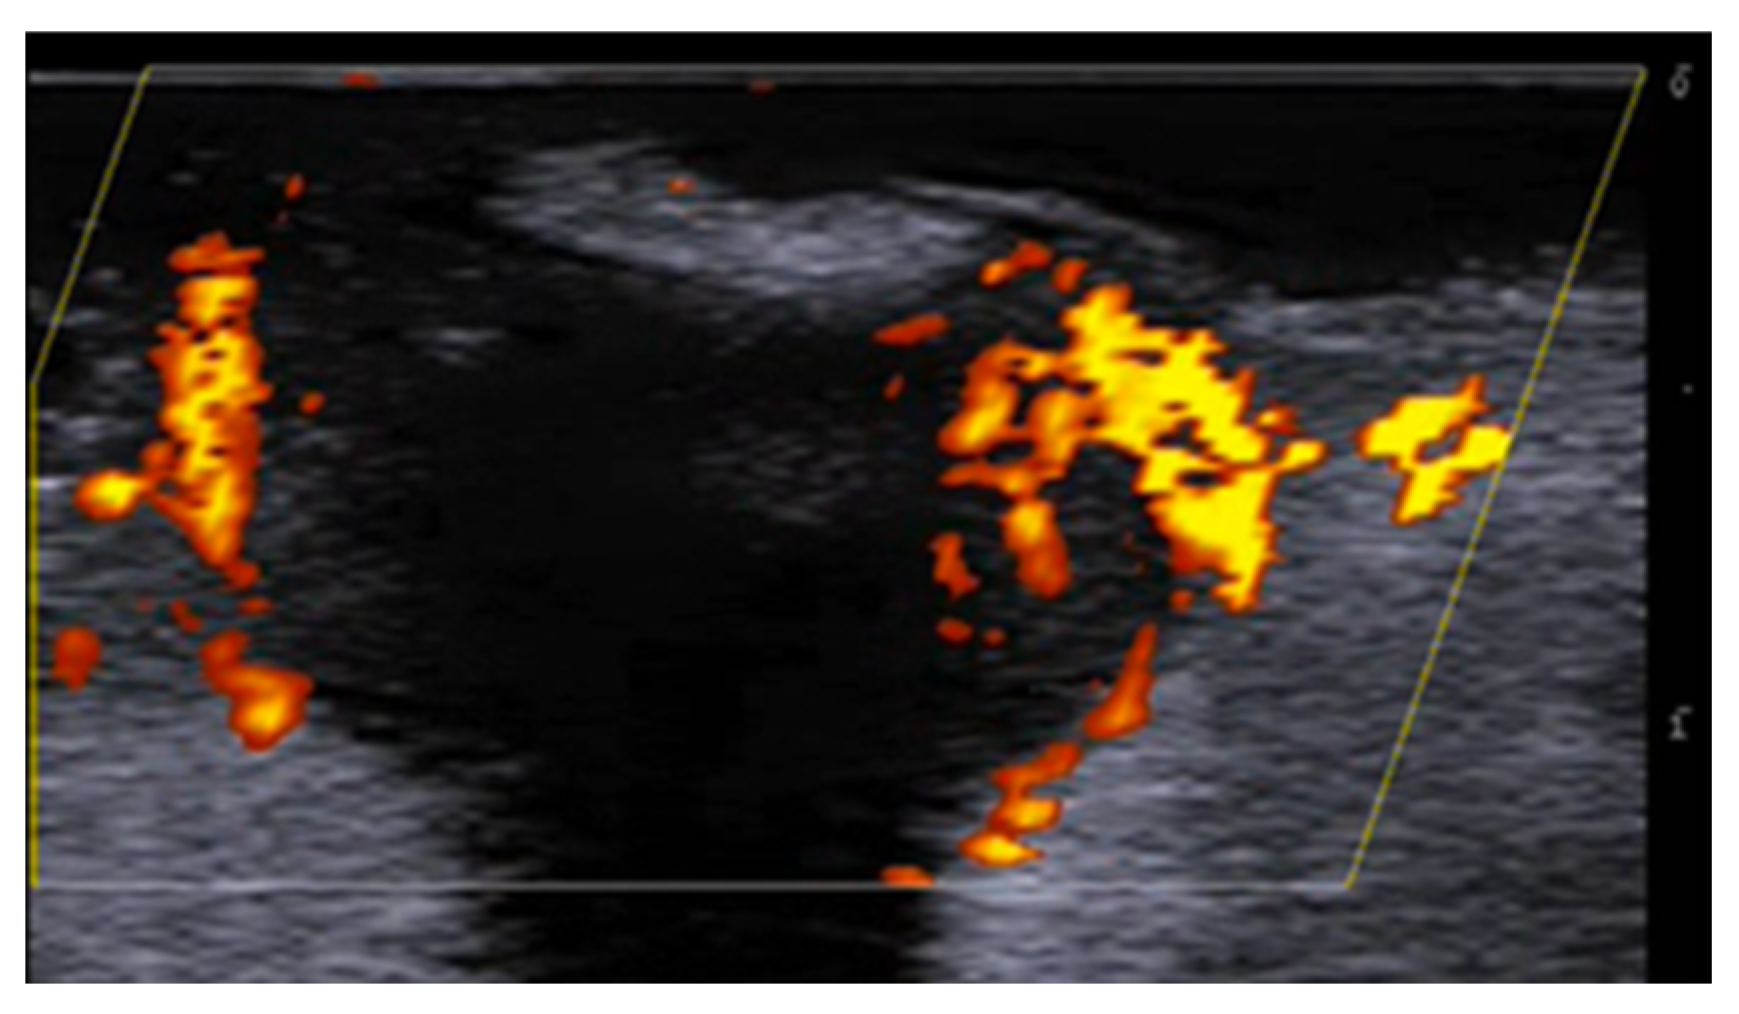

5. Specific Cutaneous Structure and Sites of Skin Disorders

6. Vascular Disorders